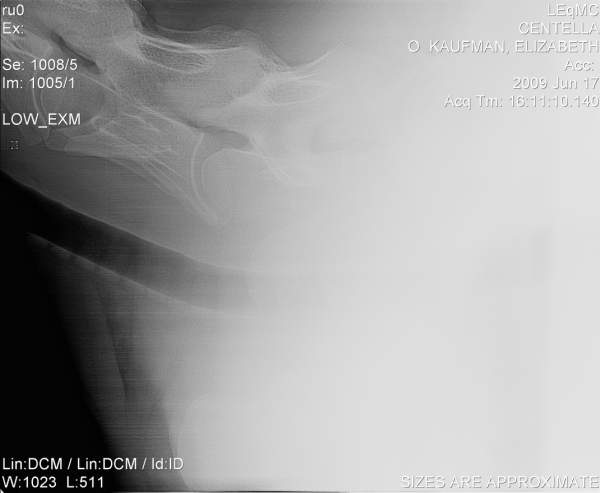

Posted on Thursday, Jun 18, 2009 - 12:01 pm: Hello DrO,I'd be curious to hear your opinion of these cervical radiographs. They are of a 7 yo horse with a history of non-performance with various low grade hind end lamenesses and symmetric poor muscle development. The neuro exam on this horse was "not quite right" on the hind end, though there were no glaring, repeatable failures.

Posted on Friday, Jun 19, 2009 - 8:15 am: Hello elk,Of all skeletal radiographs cervical vertebral radiographs are some of the very hardest to accurately interpret requiring the very best resolution, often over an hour of review with rulers, marking pens, and calculators to determine the significance of perceived irregularities. In the above images many of the facets and spinal canal spaces are not clear enough for a good evaluation. They may be fine on the orignals however. So let me turn this around and ask you did the folks reviewing the originals and hopefully spend the required time to assess the hundreds of individual points of interest in such a radiographic series find any abnormalities? I always think it wise to have such a set of radiographs with questionable findings be reviewed by a equine radiologist or orthopedic surgeon. DrO |

Posted on Friday, Jun 19, 2009 - 9:37 am: Hello DrO,The x-rays were reviewed as carefully as possible, I believe, given the experience and schedules of the folks involved. The originals are somewhat more clear, though not perfect-- it's a very big horse. Conversion to jpeg format and reduction for posting has not improved them! These x-rays also have been referred out for review. The equine surgeon who examined the horse and (with her colleagues) reviewed the x-rays was suspicious that there was evidence of DJD in C5-C7, with C6-C7 being the area most highly compromised. Based on this, the horse has been recommended to be euthanized or retired. If retired, they warned me that he may experience significant degeneration over time (rate of decay unknowable), to the point where he may become unstable or even unable to stand. This working diagnosis is somewhat influenced by the neurologic changes in the sire of the horse, who was stringhalt as he aged (at the time, attributed to neck trauma or old age). Unfortunately, I own 4 horses with these genetics, so I want to be very careful with the diagnosis. We had x-rayed every leg joint in this horse many times, never with an OCD finding elsewhere, though I understand the neck lesions can be found in horses with no other visible DJD. The diagnosis is not implausible given the history and symptoms that took the horse to x-ray. |

Posted on Sunday, Jun 21, 2009 - 10:51 am: elk, sorry for the delay I wanted to view this in my office where I have a large screen high contrast monitor. Hmmmm...the first image, which appears to be a retake of the last image to help bring out the details of C6-C7, does show a step in the articulation of the bodies of C6-C7 but I lose details of the facets and most important the margins of the the vertebral canal. This step may represent the narrowing they are discussing but my lack of regular review of such radiographs makes my interpretation subject to question.DrO |

Posted on Sunday, Jun 21, 2009 - 3:39 pm: Hi DrO, thank you.In the original format on the large viewer at Littleton, the changes you note are even clearer. C6-C7 look almost as if they were starting to fuse, and the canal appears to have narrowed such that it is most probably beginning to impinge on the spinal cord. Do you concur that, if the x-rays have been read correctly, the horse is unsafe to ride? Do you know anything about the origins, management, or progression of this condition? Littleton clearly felt that it would be progressive and eventually fatal, should the horse be left to degenerate indefinitely. They could not speculate on how rapidly that progression might occur, and felt that it was probably similar to other forms of OCD (significantly hereditary, with environmental and management factors as well). |

Posted on Sunday, Jun 21, 2009 - 10:39 pm: I see...I had presumed the loss of definition of the articular facets was with the image size and quality. The way you frame the question it is a easy call elk, if the spinal cord is being impinged, yes the horse should be considered dangerous to ride and the disease most likely progressive.Concerning your questions on origin, management, and progression they are discussed in the article. If you have specific question not covered post it back here. DrO |